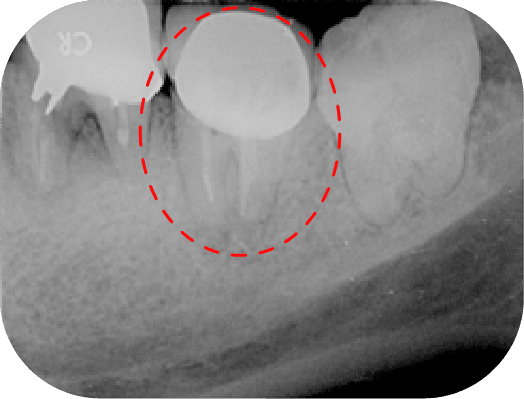

案例分享

左圖中第一大臼齒兩個牙根皆因為根管內的感染造成根尖周圍炎(紅線中黑黑的地方),在根管治療後追蹤一年可發現骨頭都已經恢復正常的樣子

上圖中第一大臼齒兩個牙根皆因為根管內的感染造成根尖周圍炎(紅線中黑黑的地方),在根管治療後追蹤一年可發現骨頭都已經恢復正常的樣子